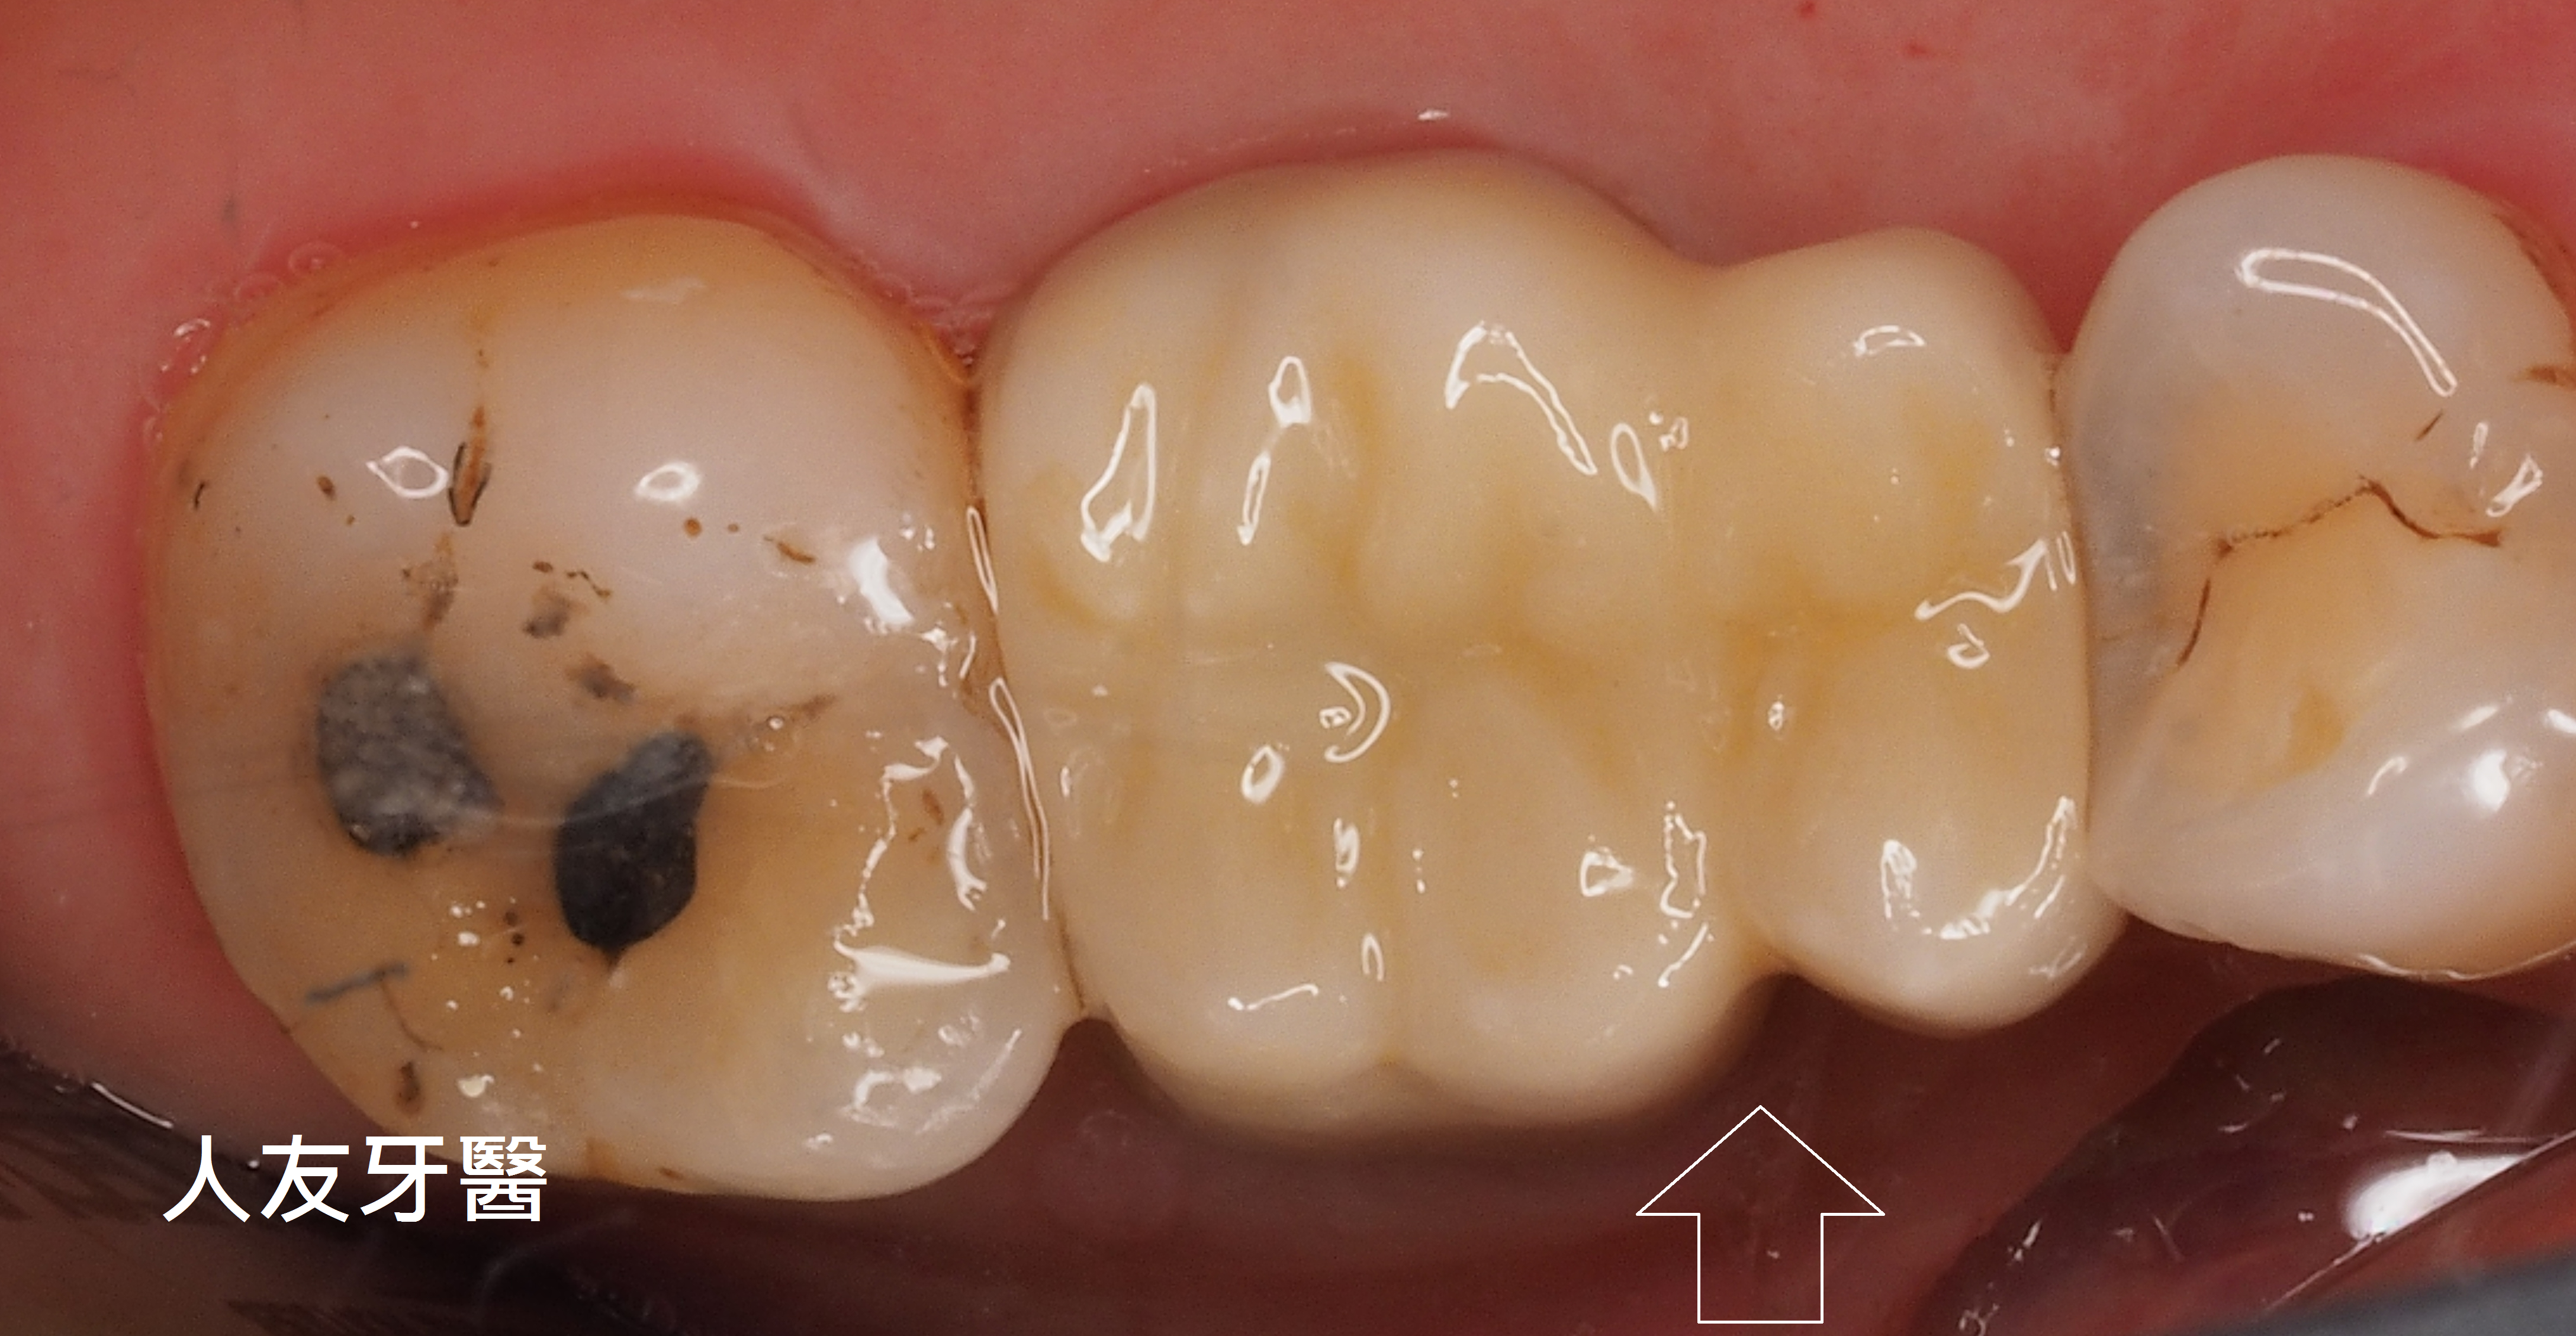

下圖是別家做的牙橋

想詢問周醫師如何處理。醫師看了X-RAY發現右邊側門牙紅色圓圈的地方有病變,有可能留不住。左邊側門牙藍色箭頭牙齒有裂到肉,也可能留不住。經過討論後建議都拔除。